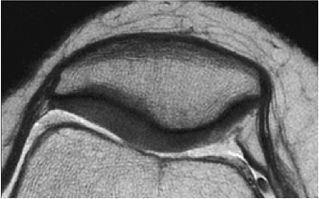

envelope, providing more efficient use of imaging time. Fast spin-echo images are cartilage-sensitive due to an inherent magnetization transfer contrast and exchange of off-resonance magnetization between slices, the net effect of which is to saturate the bound pool of hydrogen nuclei, resulting in a decrease in signal intensity from the free pool.36 This exchange results in relatively high signal intensity from fluid compared to the lower signal intensity of articular cartilage, providing an effective differential contrast among menisci, articular cartilage, and fluid in the meniscosynovial recesses (Fig. 7.5). With arthroscopy as a standard, Potter et al. found that articular surface evaluation using spin-echo sequences had a sensitivity of 87%, a specificity of 94%, and an accuracy of 92%, with minimal interobserver variability (kappa = 0.93).18 These findings of reproducibility support the use of MR imaging as a noninvasive and objective outcome measure of surgically manipulated cartilage and in the longitudinal evaluation of traumatic and degenerative cartilage lesions.

FIGURE 7.5 ● Sagittal fast spin-echo MR image of the knee in a 50-year-old patient demonstrates differential contrast for the high-signal-intensity joint fluid within the meniscosynovial recess (arrowhead), the intermediate signal intensity of hyaline cartilage, and the low signal intensity of meniscal fibrocartilage. Over the tibial plateau cartilage, note the gray-scale stratification (arrow) with lower signal intensity in the basilar components.